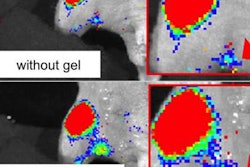

A stimulated Raman scattering (SRS) microscope helps neurosurgeons analyze tissue without the need for tissue processing, speeding up the decision-making process during brain tumor surgery. Image courtesy of NIBIB.Lead author Dr. Daniel Orringer and colleagues from the University of Michigan used a microscopy technique called stimulated Raman scattering (SRS) that eliminates the need for tissue processing, or slicing and staining the tissue. By using a fiber-laser microscope similar to the fiber optics in internet and phone cables, as well as developing a way to reduce background signals common to fiber-laser images, the group created a high-resolution system that has been validated in more than 100 patients.

The researchers also developed another technique called stimulated Raman histology (SRH). SRH is used to process the resulting images quickly by taking advantage of the chemical properties of the tissue, making proteins and DNA appear purple and lipids appear pink.

The result is similar to using hematoxylin and eosin (H&E) staining, and pathologists can interpret the images without special training. Eliminating sectioning and staining reduces processing time to about three minutes, 10 times faster than standard tissue-processing techniques. In a 30-sample analysis, pathologists came to similar conclusions using SRH and conventional techniques.